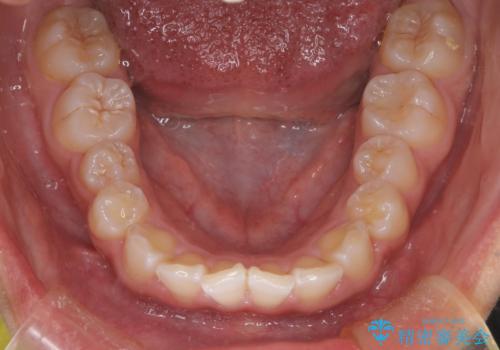

マウスピース矯正で前歯のガタツキを改善! ワイヤー矯正併用でかみ合わせもしっかり治します

- 前歯のガタツキが気になると来院されました。

マウスピース矯正治療を選択しました。

この症例では、奥歯のかみ合わせの改善を目的にワイヤー矯正を併用しました。奥歯のかみ合わせをより緊密にするため、また短期間に治療するためにはワイヤー矯正が適していることがあります。